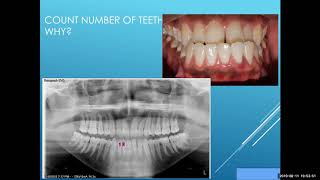

Orthodontics | Diagnosis & Treatment Planning | NBDE Part II

In this video, we delve into the soft tissue paradigm and orthodontic exam, including what to look for during the intraoral, extraoral, and cephalometric ...

clinical examination of orthodontic patient I case history

learn how to do clinical examination of orthodontic patient.. this is a continuation of case history in orthodontics.. learn orthodontic diagnosis and treatment ...

Diagnosis in Orthodontics NEET MDS

Concept-based video lectures for NEET MDS. Learn Orthodontic diagnostics process along with High Yield Exam focused MCQs relevant for NEET MDS 2020.